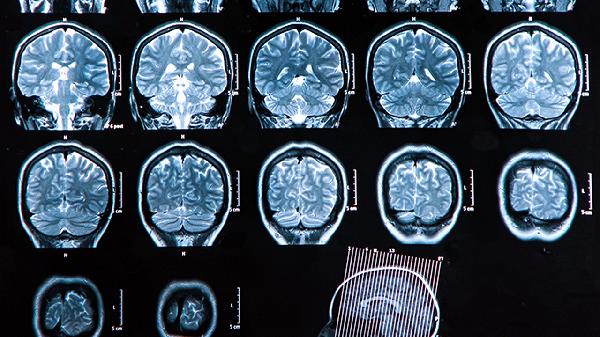

康复训练需在专业康复师指导下循序渐进进行,早期介入可显著改善预后。同时需控制血压血糖,低盐低脂饮食,戒烟限酒。定期复查头颅影像学评估恢复情况,若训练中出现头晕或肢体无力加重应及时调整方案。家属应参与训练过程,帮助患者建立康复信心。